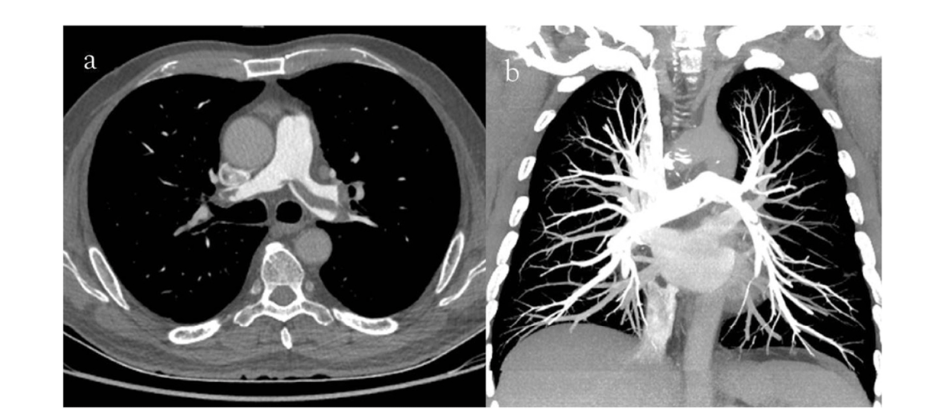

What is the protocol + pathology?

• CTPA

• There is max opacification within the pulmonary arteries therefore contrast was used and it’s in an EARLY arterial phase.

• Path = pulmonary embolism with an occlusion in the left pulmonary artery

• Filling defect characterised by hypodense streak within the left pulmonary artery.

• Coronal MIP = highest attenuation values within the voxel selected